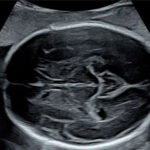

Ofrecemos servicios de ecografía obstétrica avanzada (genética, estructural, Doppler) y seguimiento experto de embarazos de alto riesgo, utilizando tecnología de punta para diagnósticos precisos